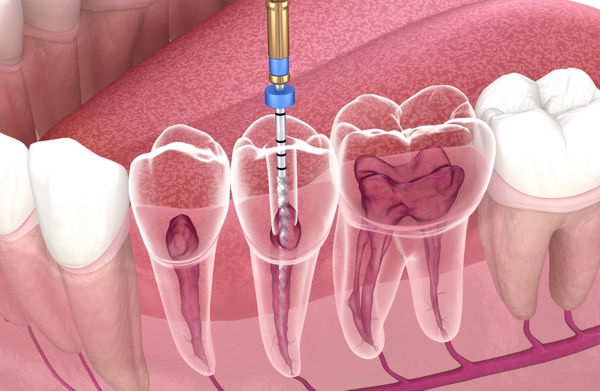

- Limpieza: Se extrae la pulpa infectada o dañada, se limpian y desinfectan los conductos radiculares.

Manejamos en la actualidad, diecisiete sistemas mecanizados tanto rotatorios como reciprocantes, porque utilizamos la práctica en forma mecanizada, (que es una computadora llamada Motor de Endodoncia, que realiza dicha práctica en forma mecanizada, dando como resultado un tratamiento más rápido, indoloro y preciso).

Realizamos siempre la endodoncia con las normas de seguridad vigentes, con Localizador Apical que nos va a orientar en la ubicación de la lima en el canal radicular, y siempre utilizamos aislamiento absoluto del campo operatorio.